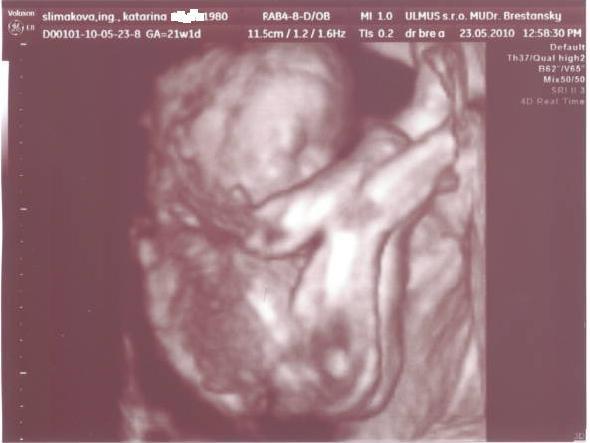

Niektoré spomienky sú silnejšie ako tie ostatné, ja nevie zabudnúť na ten pocit , keď mi pred 6 rokmi Dr. povedal, že čakám dievčatko... ja som išla odtiaľ ako na rúžovom obláčiku, usmiata od ucha po ucho, .... och tuším som dnes zase na rúžovom obláčiku 🙂